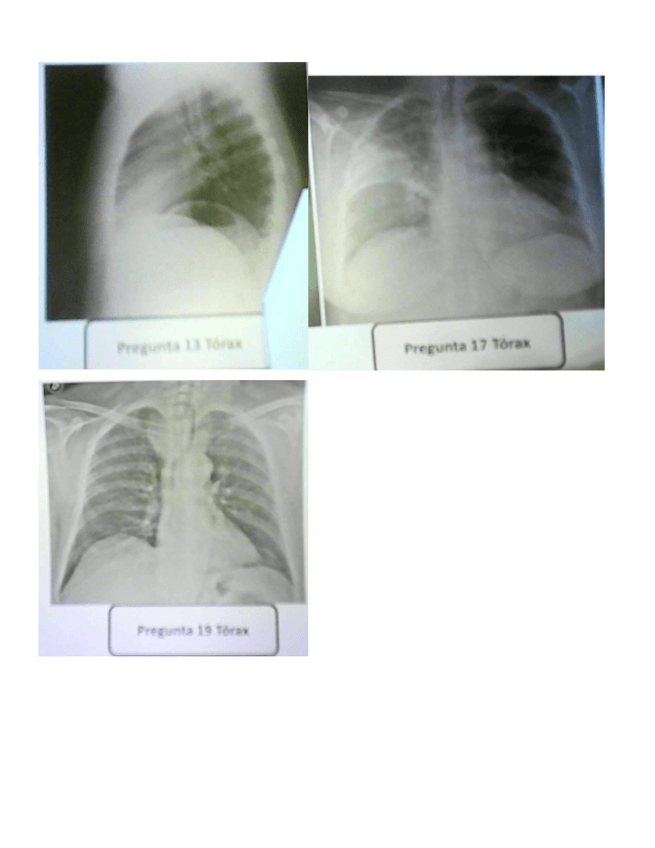

EXAMEN RAYOS ORDINARIA 2023

Dos archivos, uno con las preguntas y soluciones al final y otro con las imágenes que se han podido conseguir